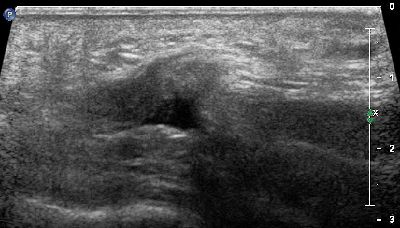

Becco osteofitico della 1a articolazione metatarso-falangea becco osteofitico prima metatarso-falangea